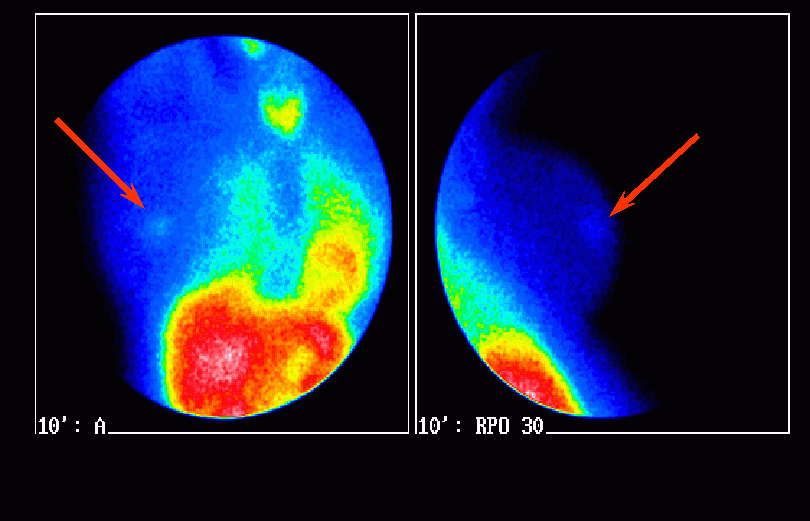

A jobb emlőbimbó alatt tapintható kb. 2 cm terime az anterior és jobb oldalirányú felvételen fokozott MIBI halmozást mutat (nyilak). A fiziológiás MIBI halmozás a pajzsmirigyben, szívben és májban jól látszik: